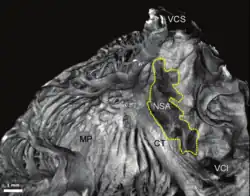

Nodo sinoauricular, con su estructura extendida característica, en un corazón de conejo. | ||

La geometría 3D del nodo sinoauricular es irregular y compleja y no está bien comprendida. Esto se debe a que el tejido de conducción no se diferencia del tejido miocárdico de la aurícula circundante, durante la disección anatómica simple.[4]

Se encuentra en la pared lateral superior de la aurícula derecha, en inmediata relación con la desembocadura de la vena cava superior. En embriología, esta zona es conocida como seno venoso (sinus venarum), de donde este nodo toma su nombre.

En la estructura del nodo sinoauricular podemos distinguir esquemáticamente una cabeza, un cuerpo y una cola. El eje mayor del cuerpo del nodo sinoauricular es paralelo a la cresta terminal, mientras que la cola penetra en dirección al endocardio. A nivel de la cabeza es subepicárdico, pues la distancia entre el nodo sinoauricular y el epicardio es de 1,5 ± 0,6 milímetros (mm); en su zona media se vuelve intraparietal y posteriormente se hace subendocárdico.[5]

Desde el punto de vista morfológico es una estructura fusiforme, con un tamaño que varía entre 5 milímetros (mm) a 30 mm, con una media de 15 mm de extensión por 5 mm de grosor variando de 1,5 mm a 5 mm, es proporcional al tamaño del corazón.